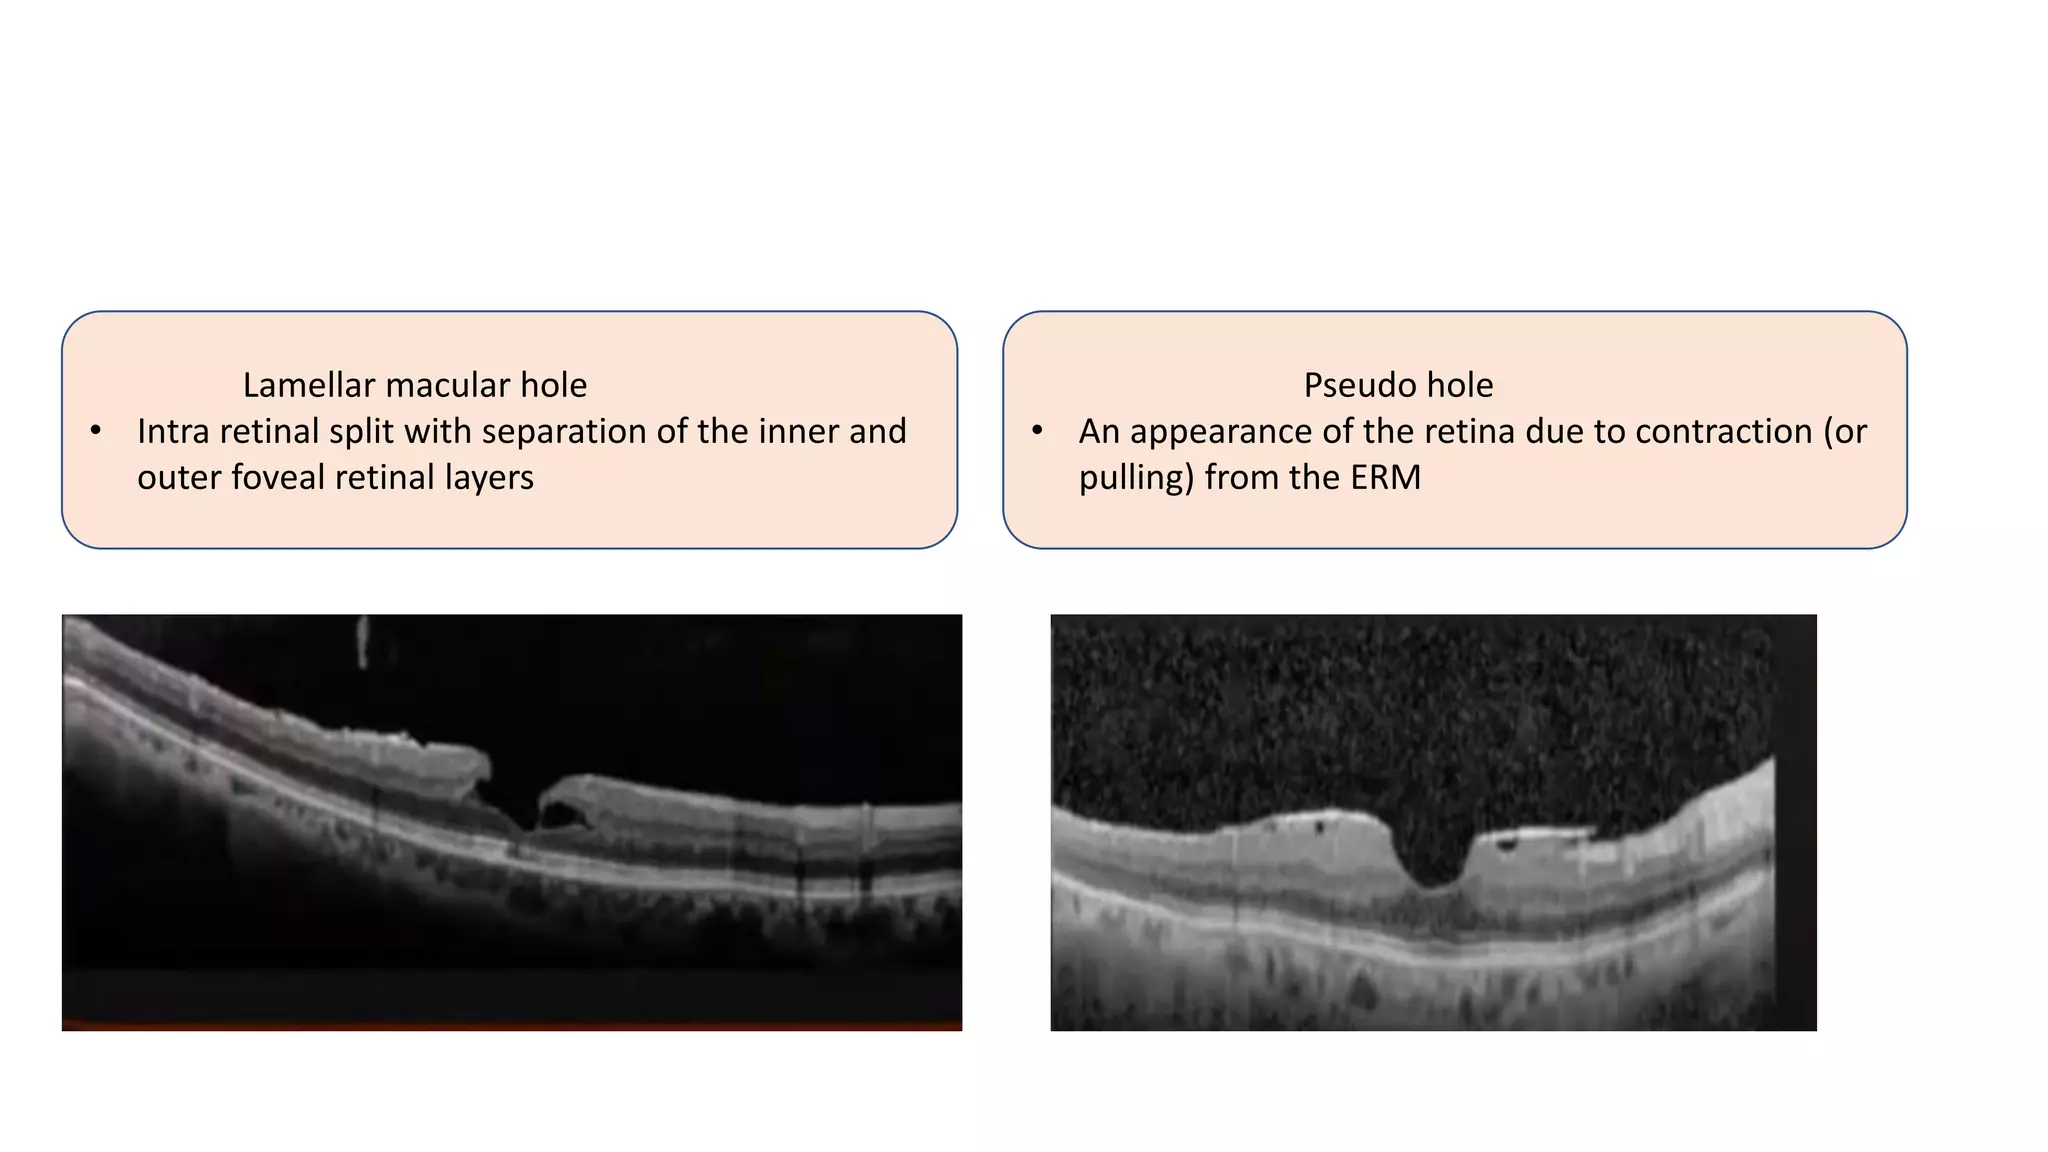

Lamellar macular hole

• Intra retinal split with separation of the inner and

outer foveal retinal layers

Pseudo hole

• An appearance of the retina due to contraction (or

pulling) from the ERM

Lamellar hole Key OCTFeatures • Irregular foveal contour • Defect of inner fovea • Separation of the inner and outer retinal layers • Lack of a full-thickness retinal defect Lamellar macular holes typically remain stable over time, and surgical treatment is rarely required.

• 67.

Lamellar macular hole •Intra retinal split with separation of the inner and outer foveal retinal layers Pseudo hole • An appearance of the retina due to contraction (or pulling) from the ERM